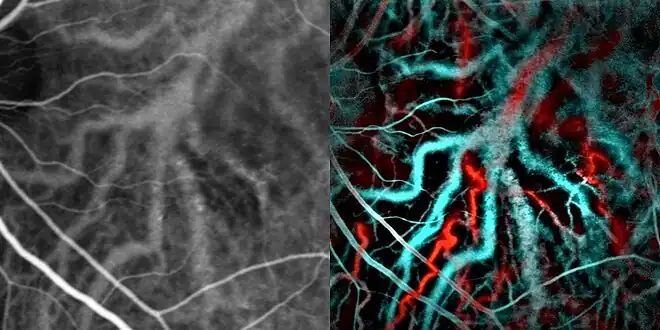

Optical coherence tomography imaging of central serous retinopathy Indocyanine green angiography (left) and laser Doppler imaging (right) of the macula in central serous retinopathy, revealing choroidal vessels. Blue and red correspond ot low and high blood flow respecively.[19]

Indocyanine green angiography (left) and laser Doppler imaging (right) of the macula in central serous retinopathy, revealing choroidal vessels. Blue and red correspond ot low and high blood flow respecively.[19]

Indocyanine green angiography or laser Doppler imaging can be used to reveal the underlying swollen choroidal vessels under the retinal pigment epithelium and assess the health of the retina in the affected area which can be useful in making a treatment decision.